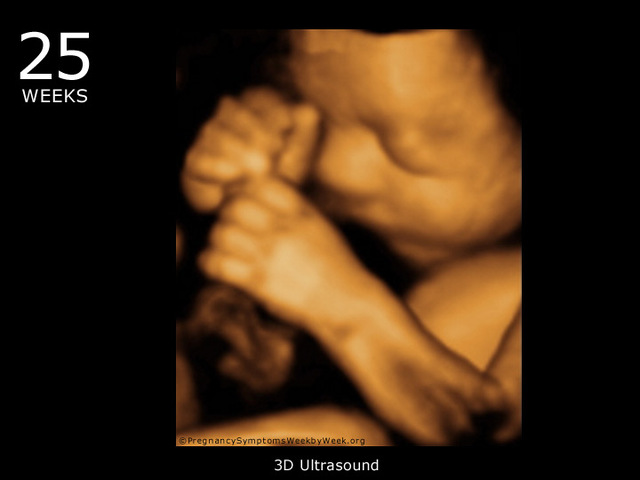

Week Twenty-five

Although your baby has it's hands, their nerve connections are still devloping as they explore themselves and your uterus. If one day, daddy want to talk to peanut, theres a higher chance that the baby will hear them better than you.